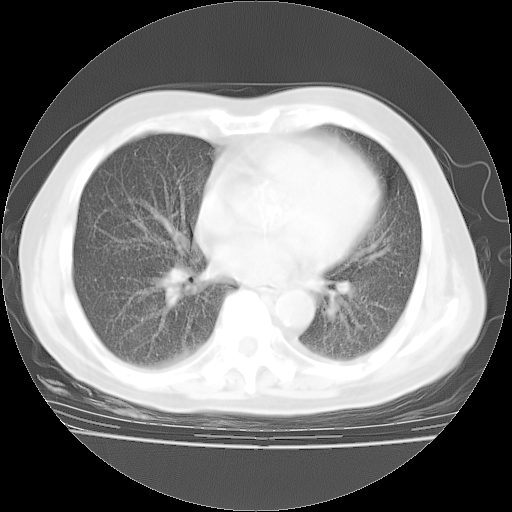

4月28日肺部CT——再次出现类似去年5月9日——透光度降低,“间质性”改变。

4月28日肺部CT——再次出现类似去年5月9日——磨玻璃样、间有“粟粒样”改变。